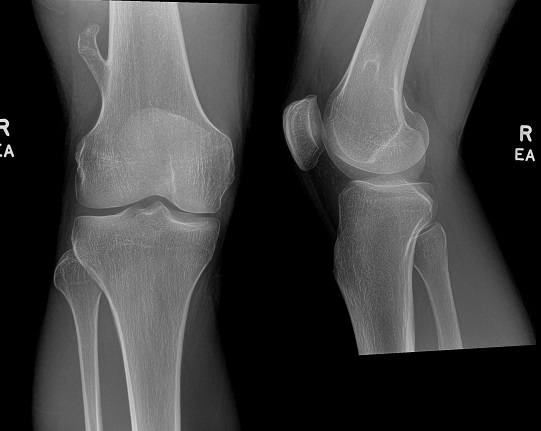

An 80 year old female presents to your office with a left ring finger deformity after a fall one week ago. She initially went to urgent care and xrays were unremarkable for a fracture (Figures 1 and 2). A photo of her left ring finger is shown in figure 3. On physical exam the left ring finger is in hyperextension at the PIP joint and flexion at the DIP joint. She able to flex her PIP joint with full motion. What is the best treatment option?